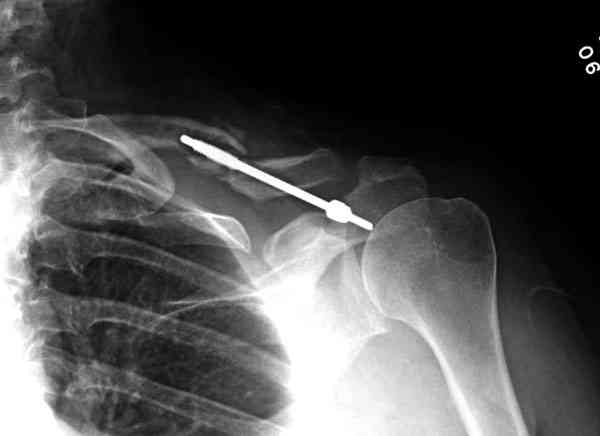

Второй случай тоже недавно оперирован по поводу

ложного сустава, в марте травма, через 4.5 половиной

операция..